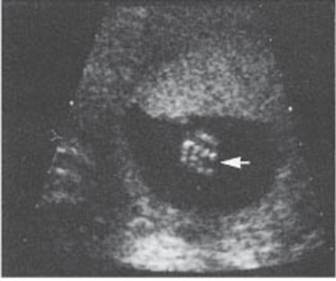

Intracardiac focus